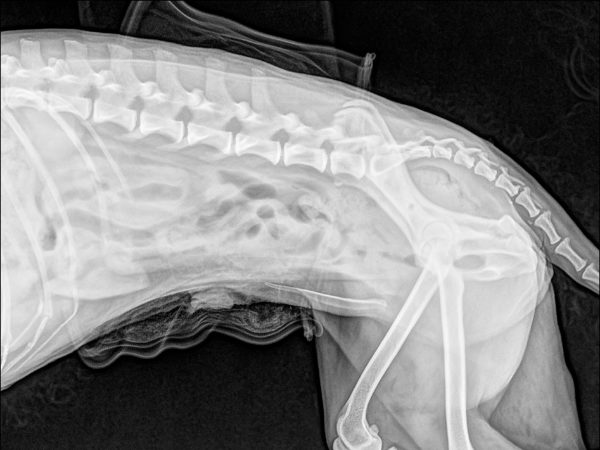

<術前のレントゲン>

左股関節が尾腹側に脱臼しています。